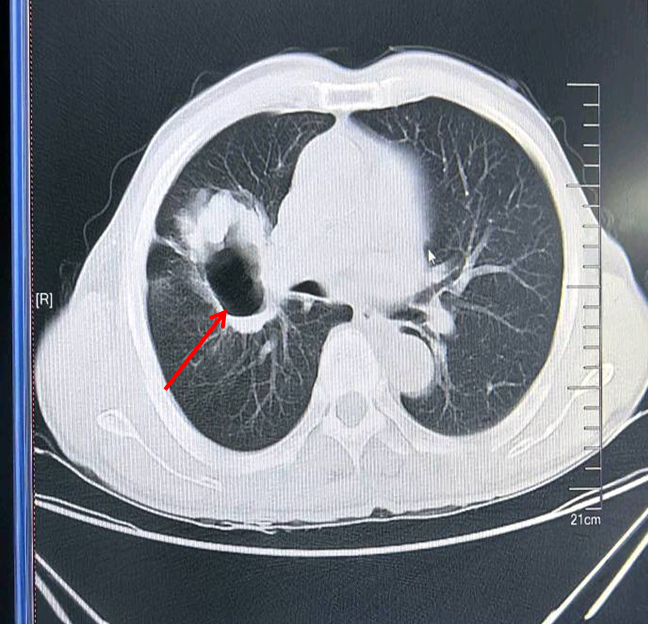

2024年3月28日,查胸部增强CT示:1.右肺中叶右肺门区肿瘤性病变(肺癌)合并空洞形成;2.纵隔多发淋巴结,部分肿大;3.右肺中上叶些许炎性病变;4.冠脉硬化;5.左侧第9、10后肋陈旧性骨折。

胸部增强CT(2024-03-28)

2024年3月29,完善肺部CT平扫增强示:1.右肺中叶支气管狭窄,局部闭塞,紧贴临近血管,病灶最大截面7.4cm×7.2cm×6.9cm,右肺中叶-石肺门区占位(考虑肿瘤性病变),合并感染并脓肿形成可能性大;2.纵隔多发淋巴结部分肿大;3.右肺中上叶多发炎性病变;4.提示贫血;5.右侧胸腔少量积液;6.肝内钙化灶,囊肿;7.双侧颈部多发淋巴结,部分稍大。心脏超声示:左房增大;左室壁增厚;二尖瓣返流(少量);三尖瓣反流(少量);主动脉瓣返流(少量);左心收缩功能减低;左室舒张功能不全(Ⅲ级)。